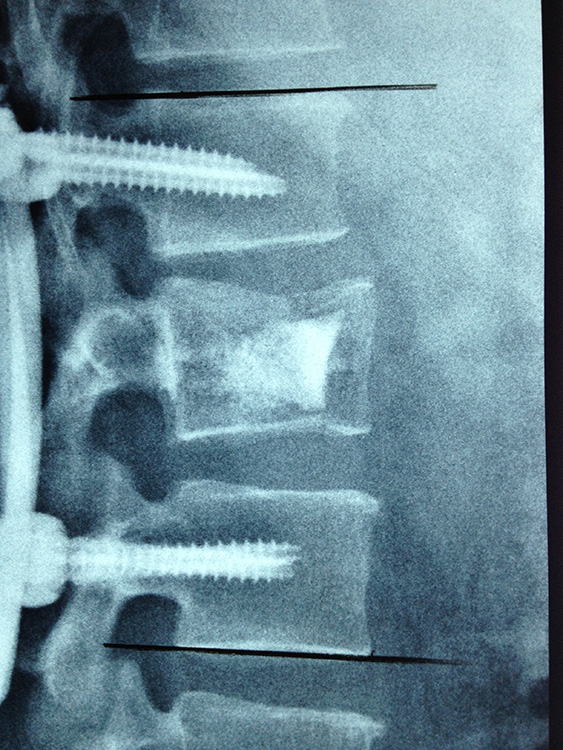

Spine Surgery

Spine Case